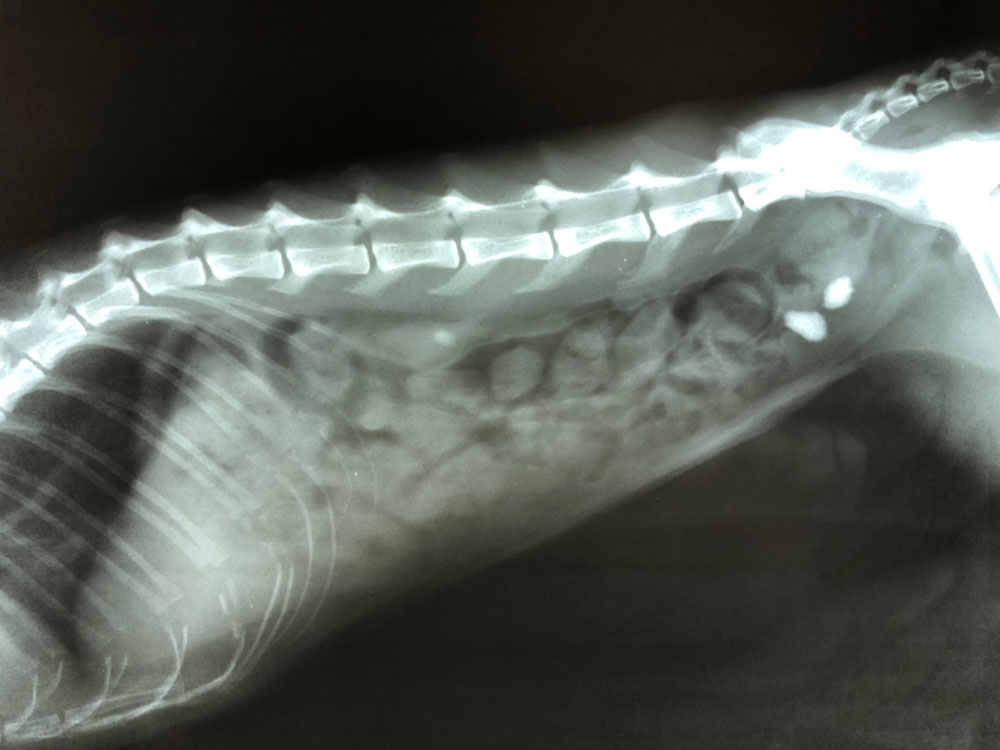

요로결석은 소변이 만들어져 배출되는 길인 요로에 결석이 생기는 질환입니다. 결석은 주로 칼슘, 수산염, 인산염 등의 무기질이 소변에 녹지 못하고 결정으로 뭉쳐져 생성됩니다.

요로결석은 신장, 요관, 방광, 요도 등 어디에서나 생길 수 있지만, 가장 흔하게는 요관에서 생깁니다. 요관은 신장에서 방광으로 소변을 운반하는 관으로, 지름이 약 5mm 정도입니다. 결석이 요관에 생기면 통증, 구역질, 구토, 혈뇨 등의 증상이 나타날 수 있습니다.